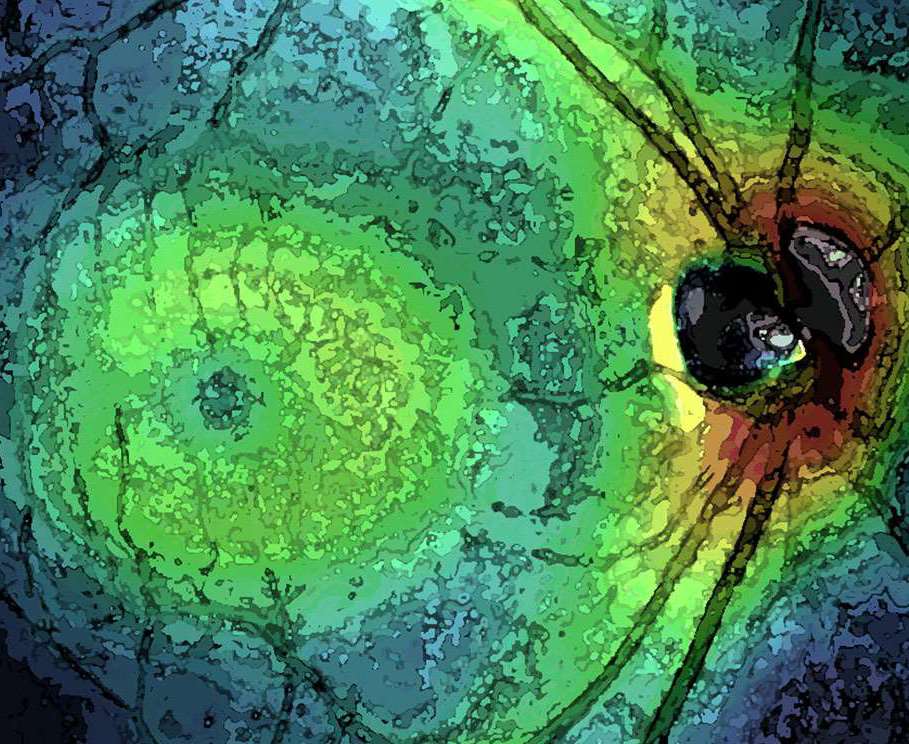

Image Gallery

The AOIP uses a wide range of imaging modalities to study the human visual system.